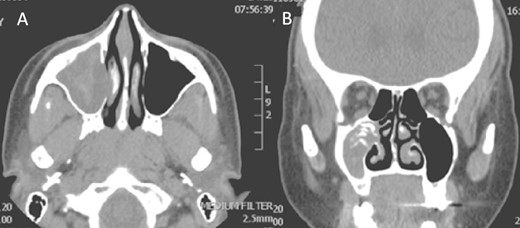

A 30-year-old lady presented to the clinic with a complaint of right facial pain, recurrent rhinorrhea with post-nasal discharge, nasal endoscopic examination was unremarkable. A non-contrast computed-tomography scan (NCCT) of the paranasal sinuses (Fig. 1) was suggestive of isolated right fungal maxillary fungal ball (FB). The patient underwent endoscopic sinus surgery (ESS) with (Fig. 2) right middle meatal antrostomy and removal of fungal debris. The patient was followed up regularly and remained symptom free.

Intra-operative endoscopic view (A) right middle meatal antrostomy showing fungal debris, (B) clean right maxillary sinus after removal of the debris.